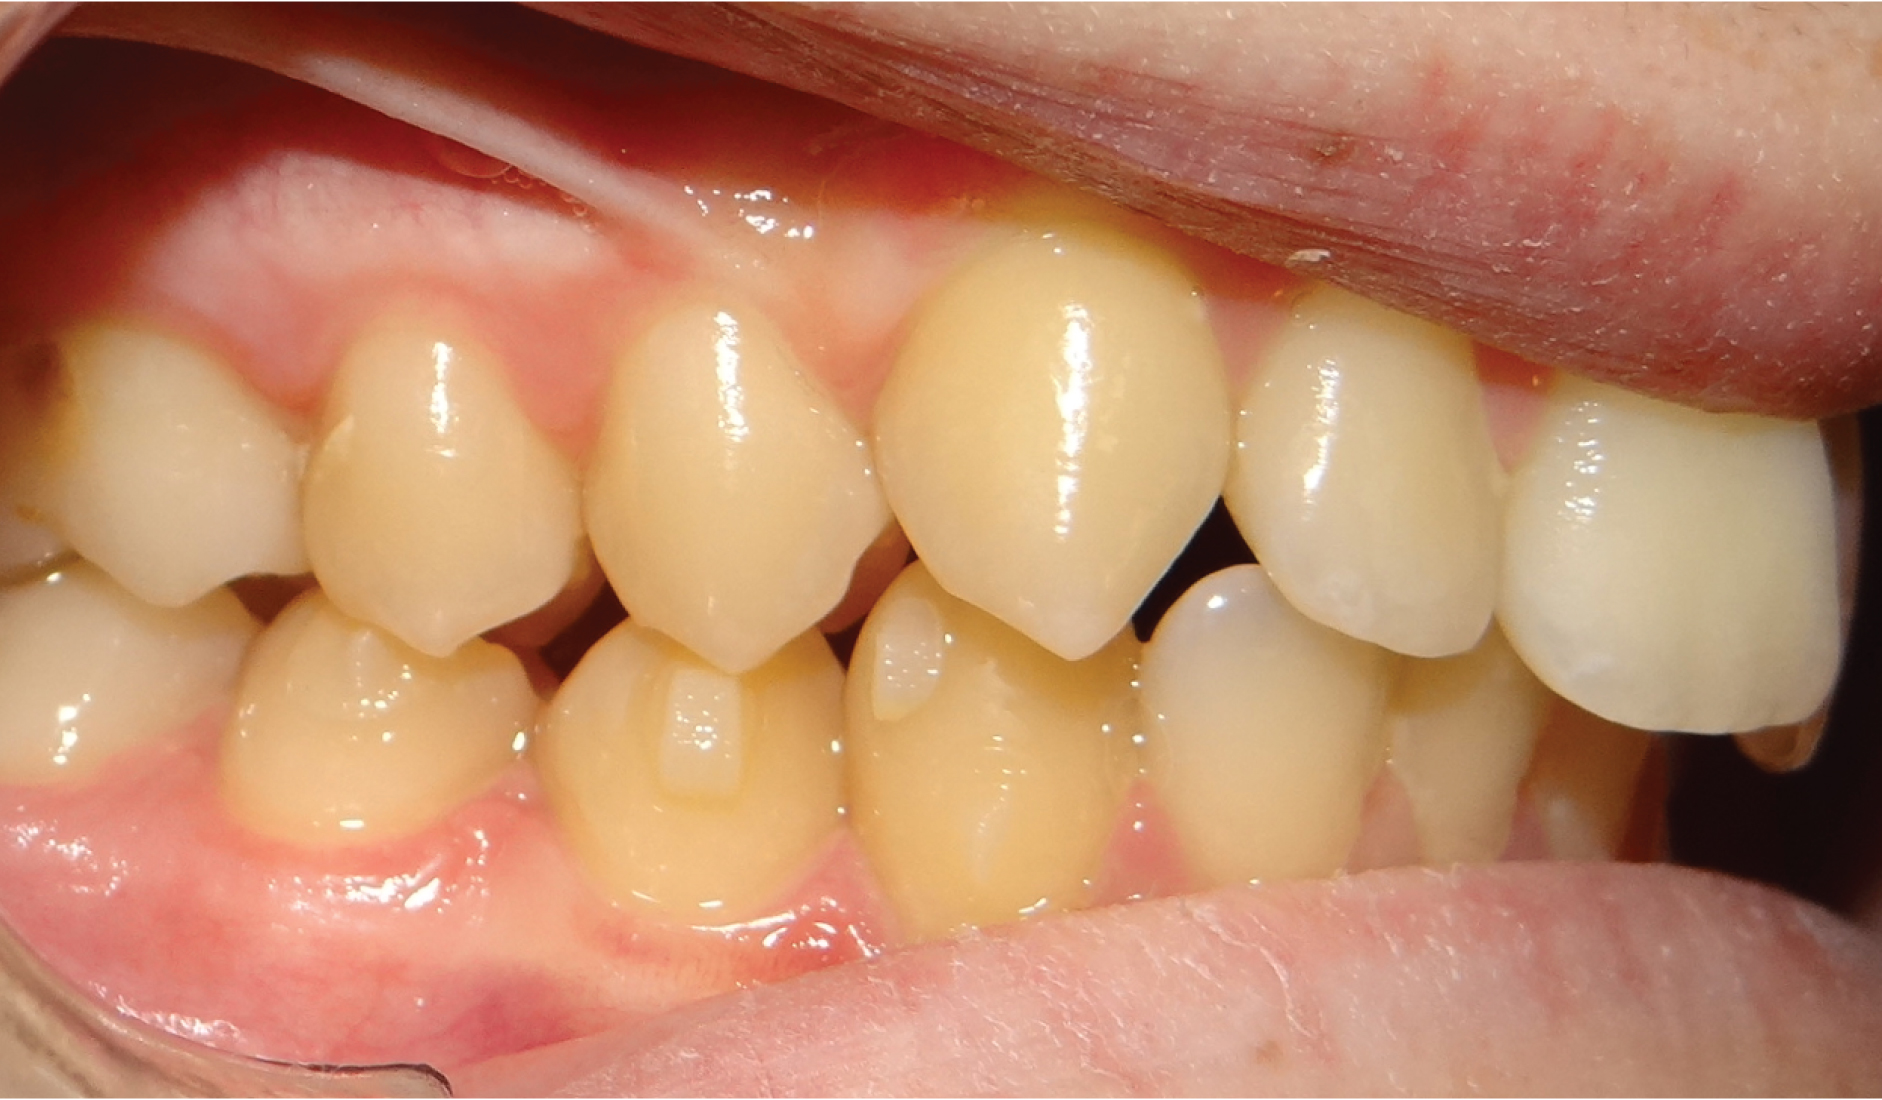

La classe II, c’est quand la mâchoire du bas est en arrière de la mâchoire du haut, donnant l’effet de “dents en avant” pour la mâchoire du haut. Si c’est normal à la naissance, Ceci paraitrait normal à la naissance et tend à se corriger avec l’allaitement maternel et la recherche de contacts entre les incisives du haut et du bas. Au plus on intervient tôt, au plus la mâchoire du bas va rattraper la mâchoire du haut ; au plus on attend, au plus on reculera le haut sur le bas avec des conséquences sur l’esthétique du profil et la capacité ventilatoire nasale.

Dans le cas d’une Classe II :

• La lèvre du bas s’interpose entre les 2 mâchoires

• Le sourire est étroit, tendance à l’écrasement du bas du visage